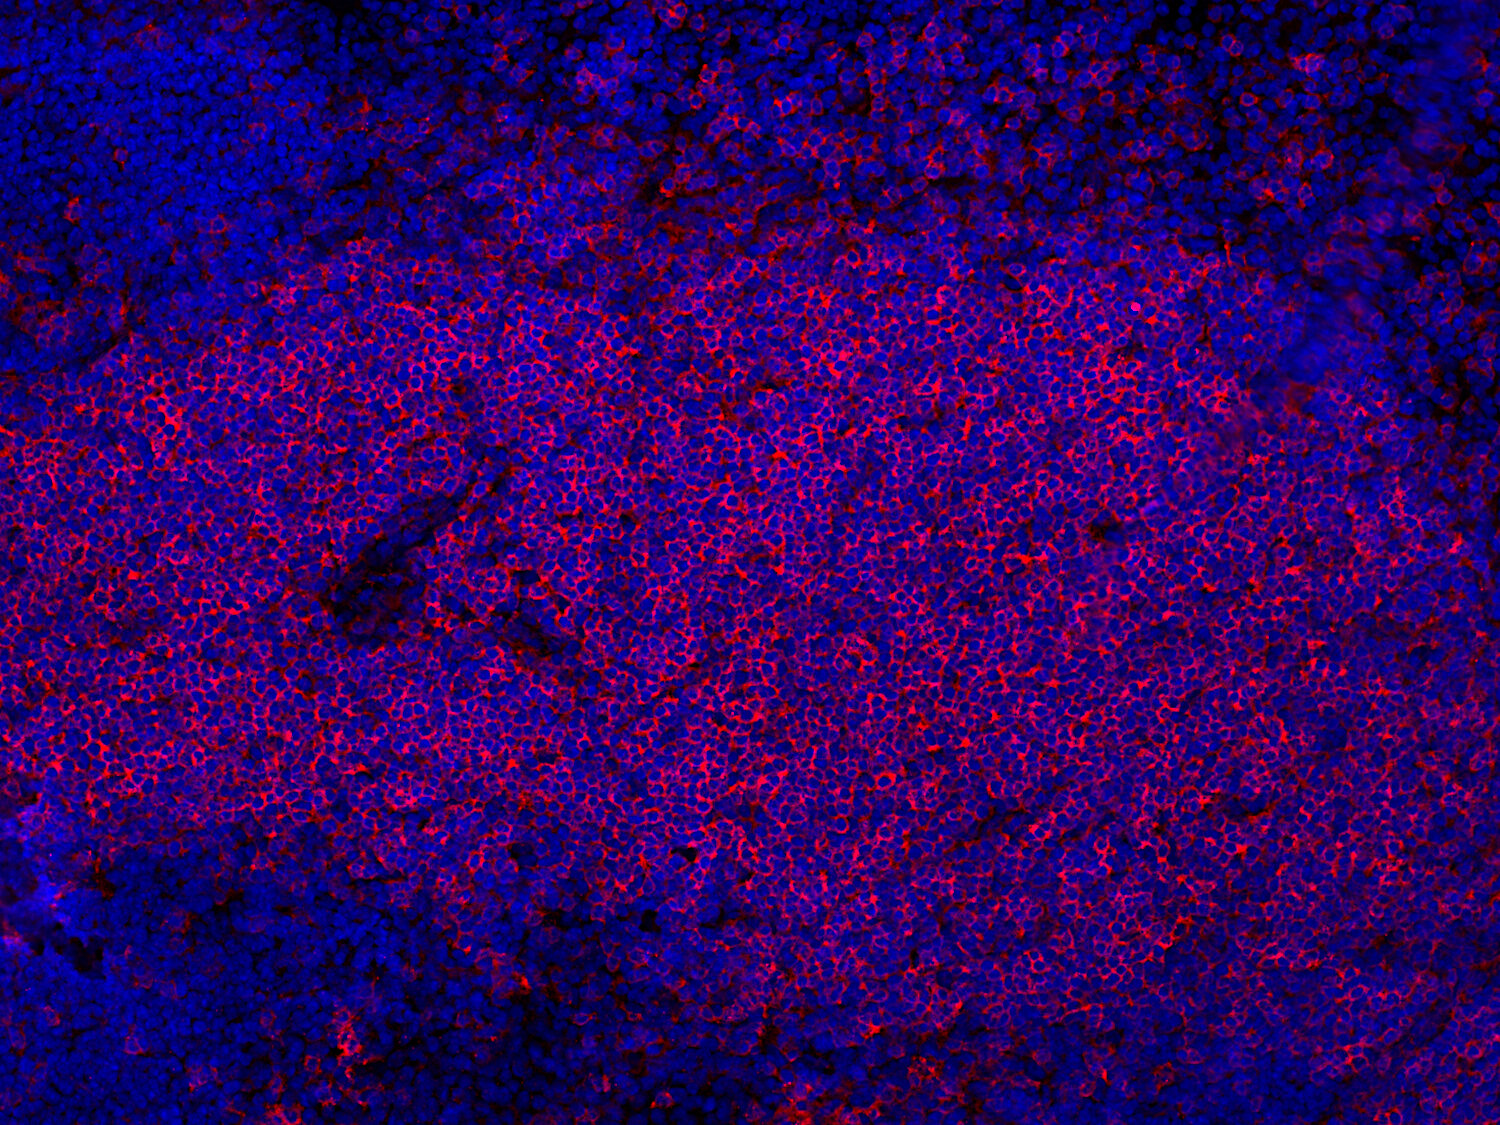

IHC-P: 1 : 900 gallery

Immunohistochemistry (IHC-P) of formalin fixed, paraffin embedded (FFPE) tissue (some antibodies require special antigen retrieval steps, please refer to the ”Remarks” section). Immunoreactivity is usually revealed by fluorescence or a chromogenic substrate.

IHC: Antigen retrieval with citrate buffer pH 6 is required.

This product belongs to the HistoSure product line of antibodies developed for and extensively tested in FFPE tissues.